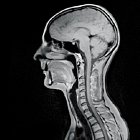

MRI stands for Magnetic Resonance Imaging. MRI is a very advanced medical imaging technique that produces very clear pictures or images of the human body in exquisite detail. It provides an excellent way to diagnose diseases of the brain, spine, abdomen, pelvis, and blood vessels.

MRI technology does not use any x-ray radiation; images are gathered through high-powered magnets. The centers use only "Short-Bore MRI Technology" which helps reduce "in-and-out" time-frame process than the average MRI scanner for those patients with a history of claustrophobia. The scanner table is outfitted with head and body soothing support which assures a very comfortable procedure.